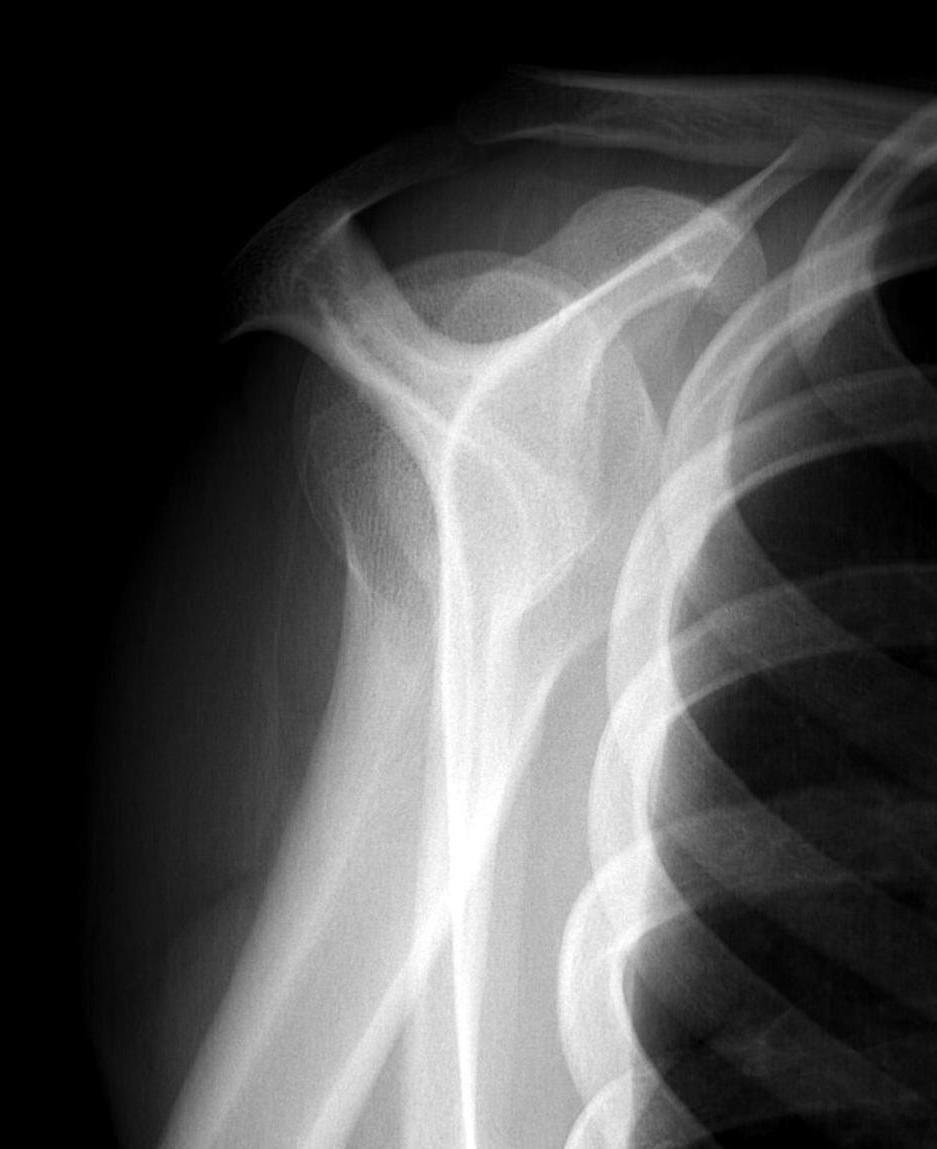

Case: 18 year old boy

Initial xray 18 month xray